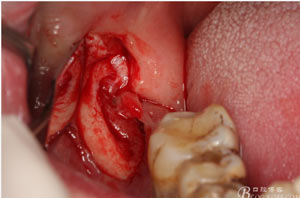

圖6.行角形瓣切開、翻瓣、暴露骨面,可見48牙冠表面有炎性肉芽組織

圖7.高速牙鉆去骨。逐漸可見48的牙冠

圖8.刮除牙冠表面的肉芽組織后,可見48 的牙冠